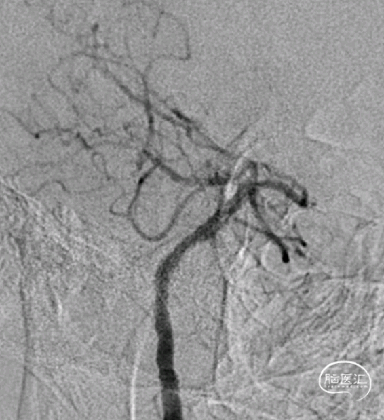

术后3月余复查:

动脉瘤愈合,支架内血流通畅。